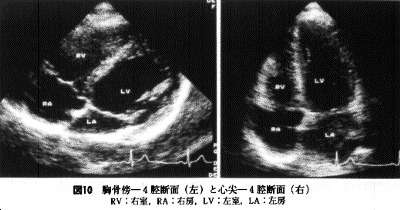

短軸断面を心尖部まで評価した状態で探触子をそのまま上方を見上げるように傾ける(探触子の頭は心尖方向に傾く)と4腔断面が描出される。この時探触子をより心尖部へ移動すれば心尖−4腔断面(apical 4 chamber view)が、前胸壁側へ移動すれば胸骨傍−4腔断面(parasternal 4 chamber view)が描出される(図10)。

4腔断面では三尖弁、僧帽弁が良好に観察されると共に右室、左室、左房、右房腔ができるだけ大きくなるように探触子にわずかな回転等を加え画像を描出する(静止画を記録する場合の時相は両心房腔が最大となる収縮末期が適している)。